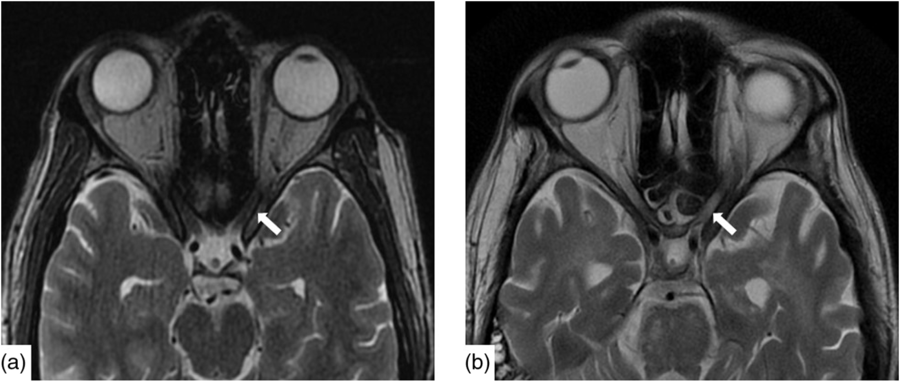

Infectious workup of blood and CSF was positive for respiratory syncytial virus (RSV) subgroup A but negative for herpes simplex, varicella zoster, tuberculosis, HIV, arbovirus, legionella, lyme, syphilis, hepatitis A, B and C, toxoplasmosis, malaria and West Nile virus. Paraneoplastic antibodies (anti-Hu, anti-Yo, anti-Ri, anti-Ma:Ta, anti-CV2, anti-Amphiphysin and anti-GAD5) were negative. Opening pressure was not measured. CT head, chest, abdomen and pelvis were all normal as was a scrotal ultrasound. Baseline magnetic resonance imaging (MRI) demonstrated nonspecific punctate foci of T2-weighted (T2W) Fluid-Attenuated Inversion Recovery signal hyperintensity, in the cerebral white matter with normal cerebral morphology and normal appearance of the optic nerves (Figure 1a).

Figure 1: Axial T2W imaging demonstrated baseline (a) normal signal intensity of the canalicular segment of the optic nerves. Within 2 months, (b) there is new, notable signal hyperintensity in the optic nerves bilaterally.

Nineteen days after admission pupils became sluggish, then 2 weeks later, became non-reactive to light with absent corneal and gag reflexes. Two months after presentation, he remained intubated and no objective determination of visual function could be obtained. Both pupils were fixed and unreactive to light. He also had bilateral lagophthalmos, severe dry eye and filamentary keratitis. Both optic discs were pale with circumpapillary high water marks suggestive of resolving optic disc oedema. In the left eye, there were flat white peripapillary retinal lesions extending into the macula, consistent with retinal nerve fibre layer infarcts. Repeat MRI demonstrated striking new T2W hyperintensity in the optic nerves (Figure 1b). Over 4 months, the retinal lesions gradually regressed followed by the high water marks, but the discs remained pale. The filamentary keratitis improved with aggressive lubrication and as he regained consciousness and the ability to blink. MRI 6 months after presentation revealed severe, global volume loss, including striking atrophy of the optic chiasm. There was also confluent, extensive signal abnormality throughout much of the brain (Figure 2). The patient was improving clinically but unexpectedly died 10 months after admission to hospital from respiratory complications.